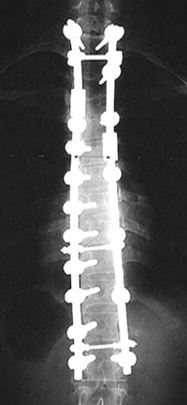

수술적 치료

만곡이 40도 이상인 경우에는 척추고정술을 통해 수술적인 치료를 시행합니다.

척추측만증변형수술

교정전

교정후